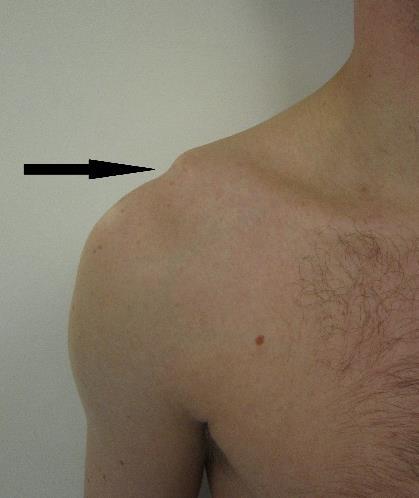

AC-luksasjon (acromioclavicularleddet):

• Hel eller delvis avrivning av leddbånd mellom ytre del av krageben og benets utspring på skulderbladet • Opptrer ofte ved fall hvor man lander direkte på skulder, f. eks sykkel eller motorsport • Kan være vanskelig å skille fra brudd i ytre del av kragebenet eller skulder ute av ledd.

AC-luksasjoner

Tegn på luksasjon, brudd eller muskelavrivning: • Feilstilling/forkorting av armen kan forekomme, f.eks. «trappetrinn» • Overarmen kan være vridd utover (95 % av luksasjonene skjer fremover) • Overarmen kan henge rett ned • Smerter direkte over AC-leddet • Smerter, mest i skadeøyeblikket, kan avta noe etter hvert ved helt avrevet muskel • Avrevet biceps kan se ut som en ”Skipper’n-muskel” (tydelig ”kul”) Andre generelle tegn og symptomer på skade: • Pasienten holder ofte armen inn mot kroppen • Nedsatt funksjon • Kan få hevelse over skadestedet • Smerter ved bevegelse (om man klarer å bevege armen)

Inspeksjon: Se etter sikre bruddtegn og hevelse, vurder sidelikhet. Ved skulder ute av ledd kan man se trappetrinn i skulderen.